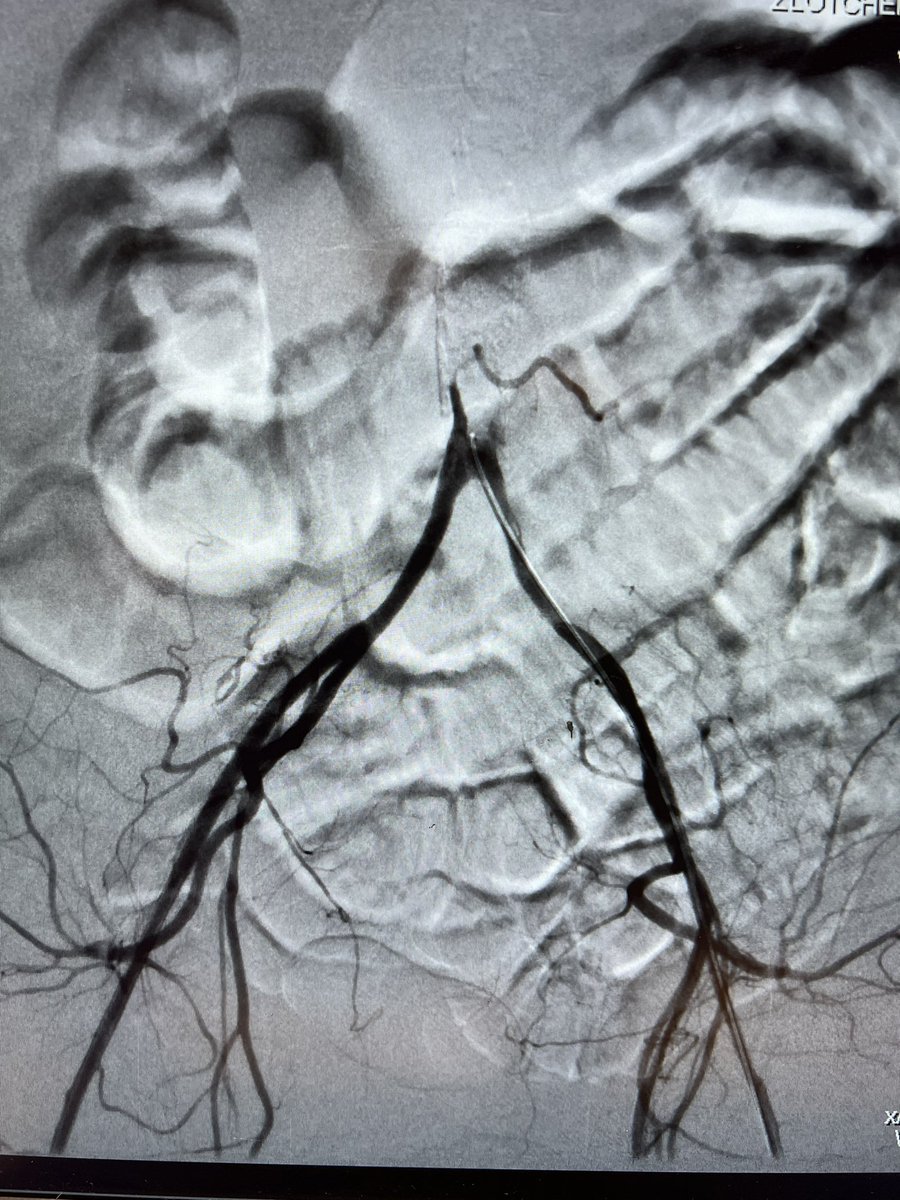

Aortoiliac occlusive disease with significant claudication s/p CERAB technique with 11mm VBX at aorta (post dilated to 16mm proximally and 14 distally) and 8mm kissing VBX with our very own @GZlotchenko @pj_rochon @LWalkerMD @CURadiology @SIRspecialists @SIR_ECS

6

17

89